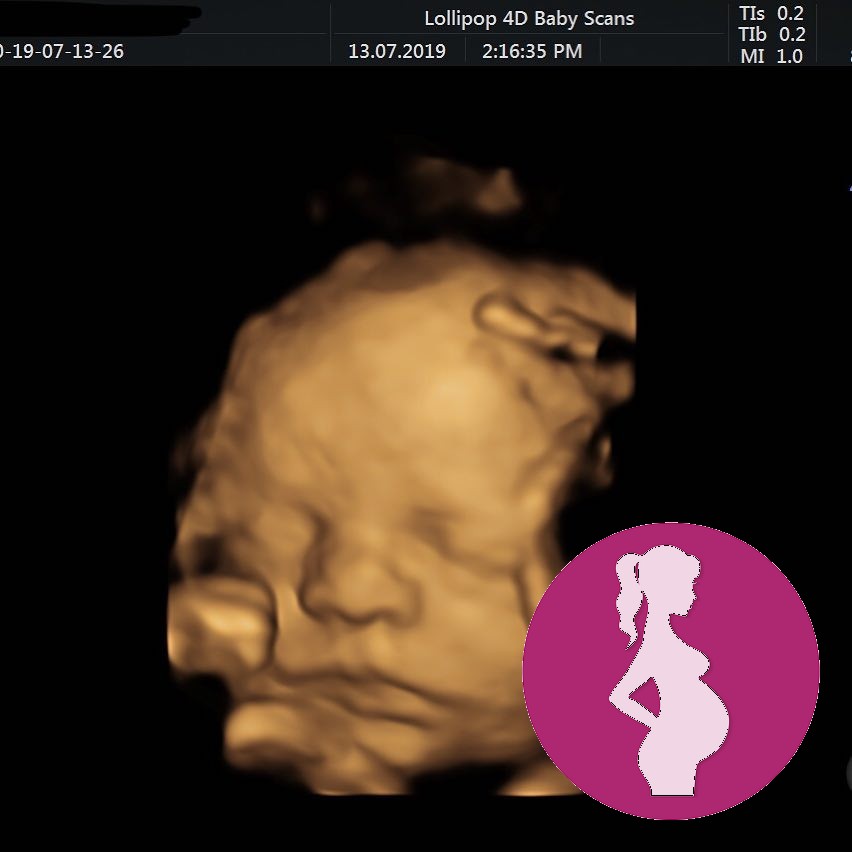

Tuesdays private 10 week scan ❤

There was an awful 30 second pause before the ultrasound technician found the heartbeat and we really feared the worst for a moment 🙈

But thankfully heartbeat was nice and strong and growth is on track (a couple of days ahead) we even saw him/her wiggling about ❤

We are now on yet another fortnight countdown to the next scan which is an NHS one at 12w2d

Still keeping everything crossed that he/she continues to stick around 🤞🤞